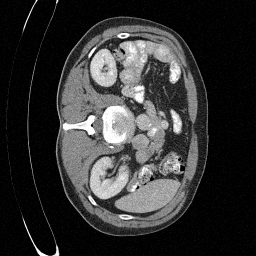

Training an NCSN on Abdomen CT - I

Figure 2: Some example images from the validation split.

Figure 1: Some augmented example images from the training split.